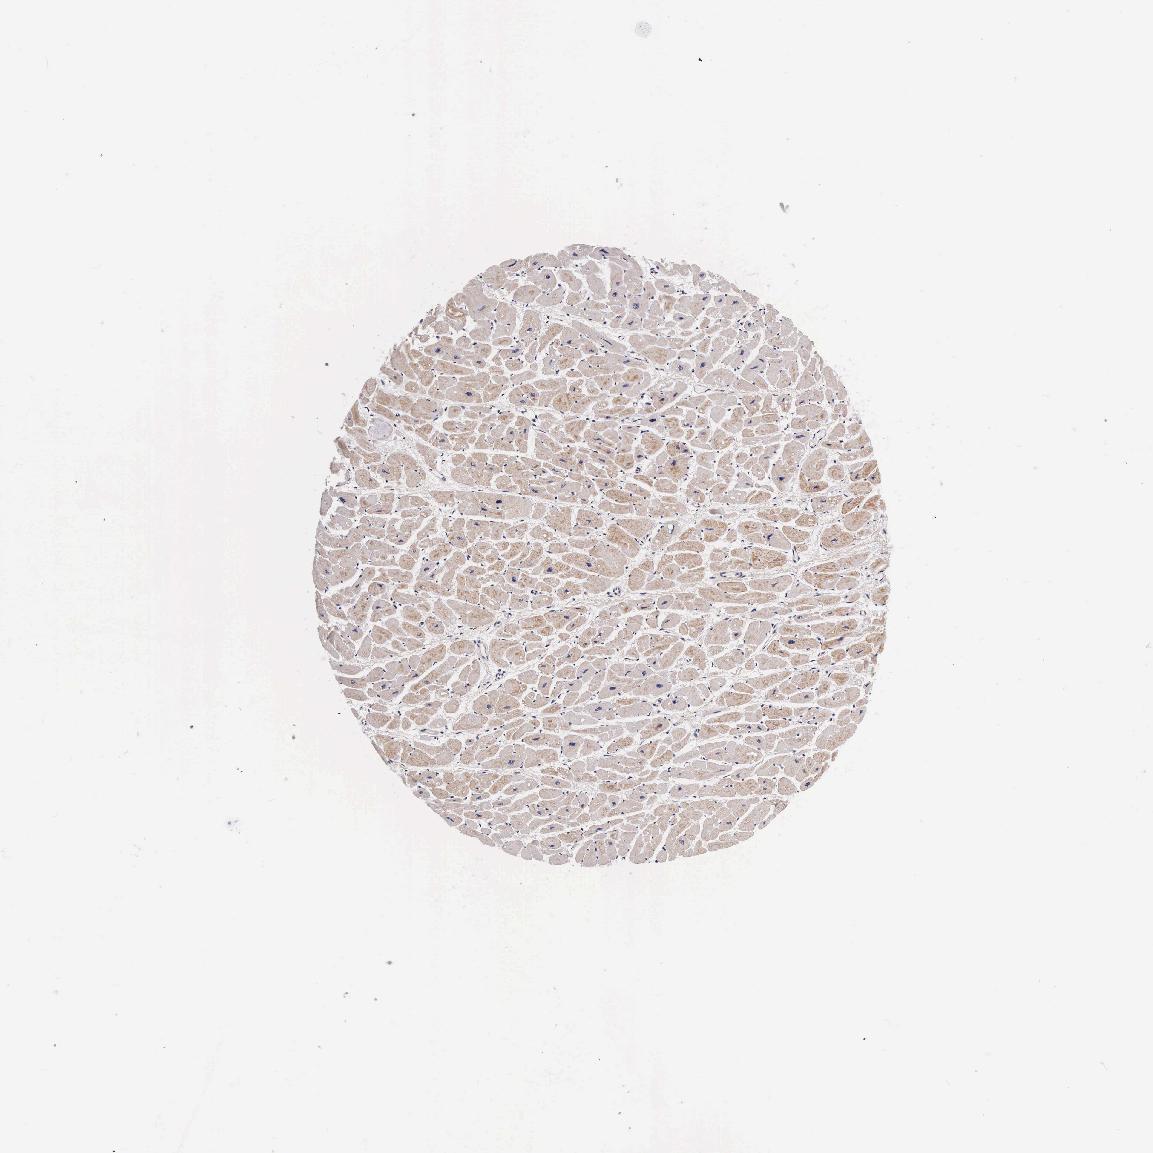

HEART MUSCLE - Antibody stainingi

Antibody staining in the annotated cell types in the current human tissue is reported as not detected, low, medium, or high, based on conventional immunohistochemistry profiling in selected tissues. This score is based on the combination of the staining intensity and fraction of stained cells.

Each image is clickable and will lead to virtual microscopy that enables deeper exploration of all samples and also displays staining intensity scores, fraction scores and subcellular localization as well as patient and tissue information for each sample.

Antibody HPA000647

Cardiomyocytes Low